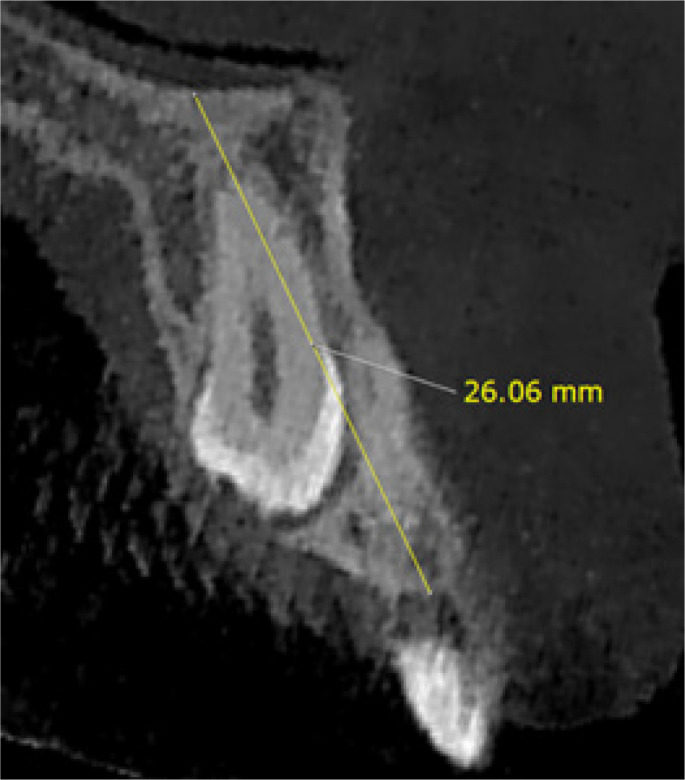

Material and methods: In this cross-sectional descriptive-analytical study, 47 CBCT images of unilateral buccally impacted maxillary canines and 47 CBCT images of unilateral palatally impacted maxillary canines were examined. Several morphological variables were compared between the impacted and non-impacted sides, and between the buccal and palatal impaction types.

Results: Gender and age were not significantly associated with the canine impaction type. The alveolar bone height at the impacted side was significantly greater in the buccally impacted group than in the palatally impacted group (p = 0.016). In a comparison of the impacted and non-impacted sides, all variables of alveolar bone thickness at depth of 2 mm, maxillary arch width, and palatal volume had significantly smaller values in the impacted side in both buccally and palatally impacted groups (p < 0.05). The alveolar bone was significantly thicker at the depth of 10 mm in the impacted side of the buccal group (p = 0.024). The maxillary arch perimeter was significantly smaller in the impacted side of the buccal group (p = 0.008). The palatal depth did not significantly differ between the groups.